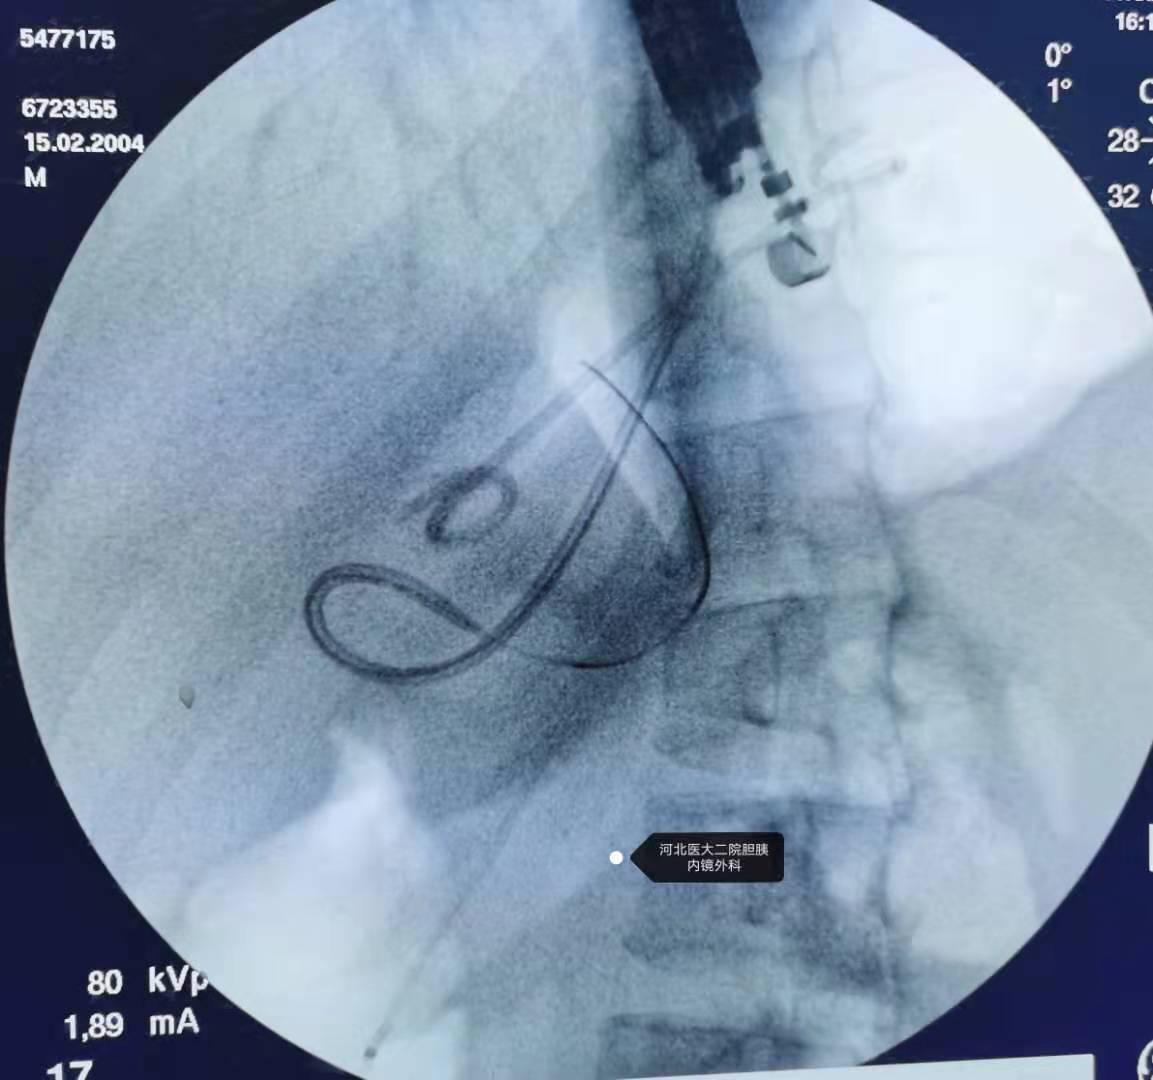

置入双猪尾支架和鼻囊肿引流管。

换双导丝。

下支架。

下鼻囊肿引流。